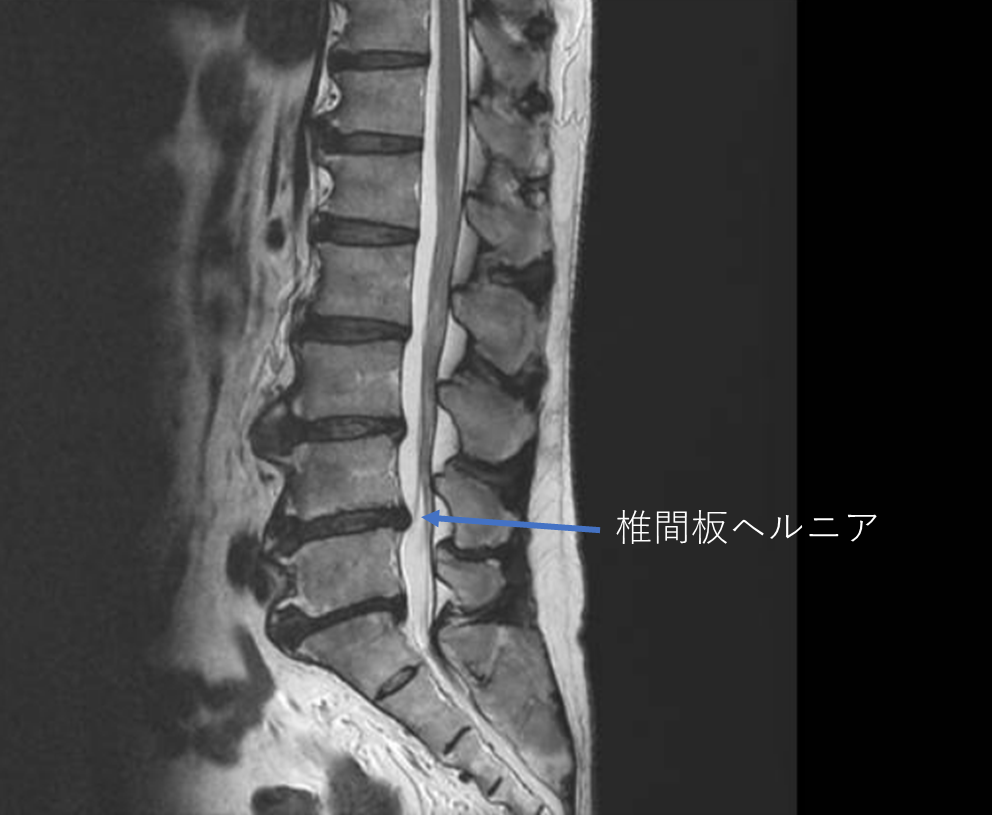

画像及び所見について

- L1/2,2/3,3/4,4/5,5/s-椎間板変性

- L4/5-椎間板ヘルニア

以上の事が画像上認められます。

・L4/5-椎間板ヘルニアを認め、主症状の原因・繰り返されるぎっくり腰の要因の可能性が高い

・L5/s-椎間板変性を認め、下肢症状の痛み・しびれの要因の可能性がある